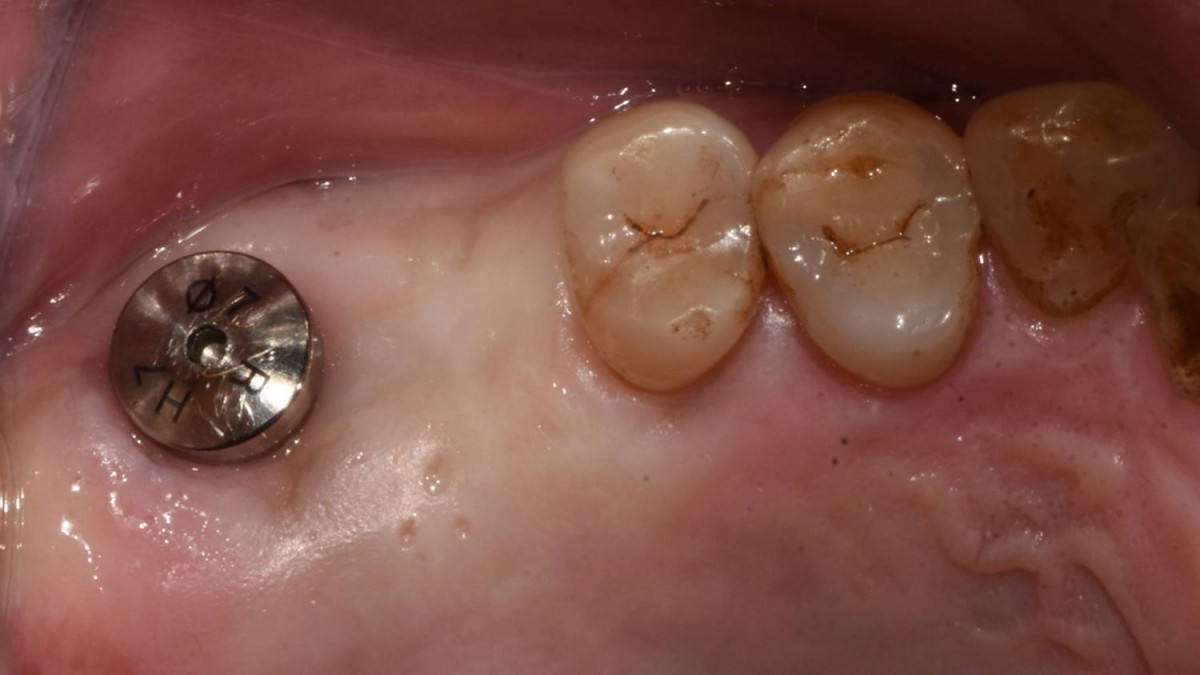

Maxillary Sinus Graft, 2 Implants, Crown Contouring

<GCaks> A 56-year-old male patient had pain-inducing caries, and perio-involved tooth mobility resulted in a tooth fracture at 1st molar. And it was removed months ago. He was a heavy smoker and showed poor oral hygiene.